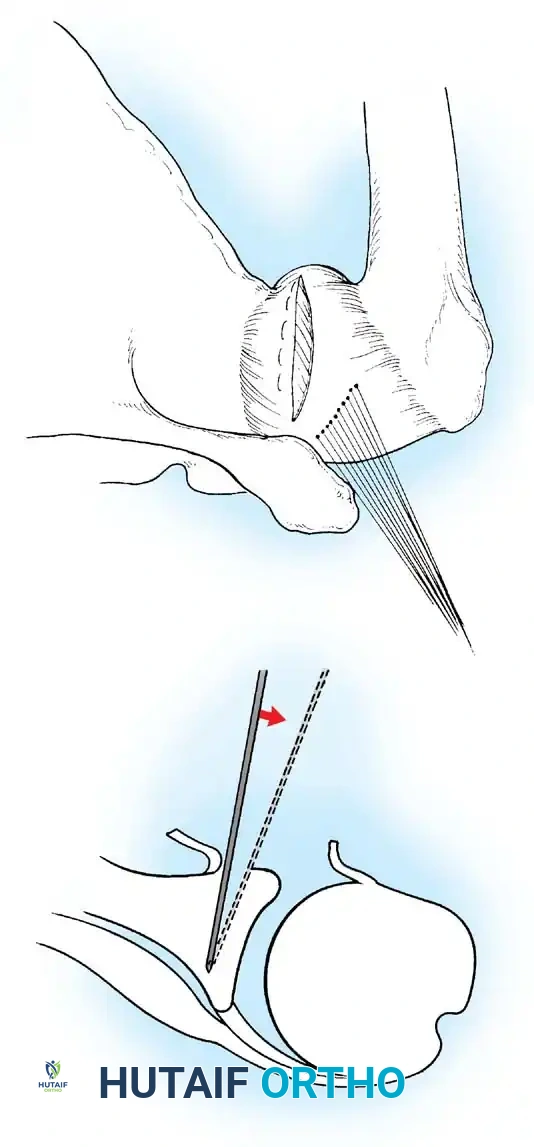

Glenoid Preparation and Labral Repair

The essential step in restoring stability is the anatomical reduction of the capsulolabral complex to a bleeding bone bed on the anterior glenoid rim.

- Debridement: The anterior glenoid neck is decorticated using a motorized burr, rasp, or osteotome to create a bleeding cancellous bed. This promotes robust biological healing of the repaired labrum.

- Mobilization: The scarred, medially displaced labrum (ALPSA lesion) must be fully mobilized using a periosteal elevator until the subscapularis muscle belly is visible anteriorly. The tissue must float freely to be shifted superiorly and laterally.

- Anchor Placement: Suture anchors (typically 3 to 4) are placed along the articular margin of the anteroinferior glenoid (from the 5:30 to 3:00 positions for a right shoulder). Anchors must be inserted at a 45-degree angle to the articular surface to maximize pullout strength and avoid joint penetration.